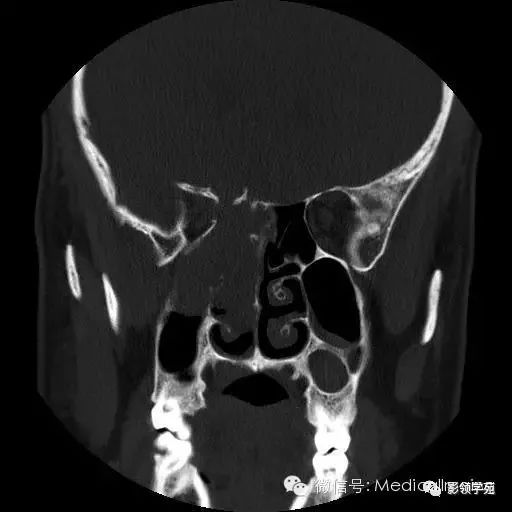

鼻窦恶性肿瘤